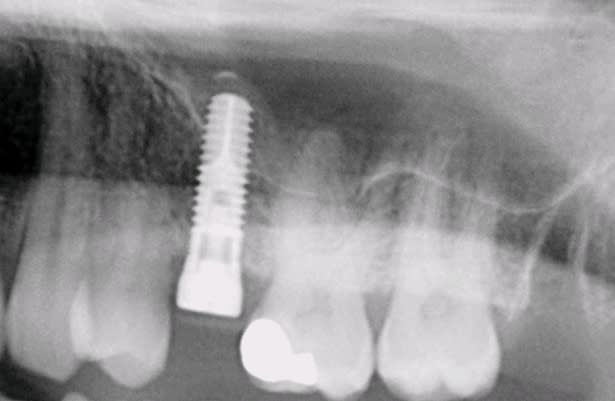

c'est la 2ème fois que fais une élévation de sinus par voie alvéolaire. La technique est rapide et non invasive et surtout simple (pour un débutant comme moi). Le petit dôme radio-opaque à l'apex de l'implant fait plaisir à voir.

7mm de hauteur d'os disponible

Implant 10mm x 5 (Seven de M.I.S)